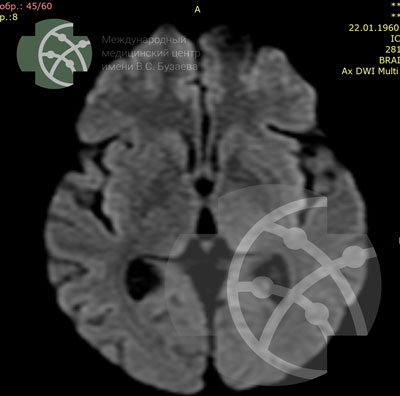

DWI* axial / 4 мм

*MRI sequence — DWI и ADC

Clinical Application:

- Early Detection of Ischemic Stroke

- Differentiation Between Early and Late Stroke

- Differentiation between Epidermoid and Arachnoid Cyst

- Differentiation between abscess and tumors with necrosis

- Detection of Cortical Lesions in the Brain

- Differentiation between herpes and diffuse glioma

- Staging of Gliomas and Meningiomas

- Demoralization assessments